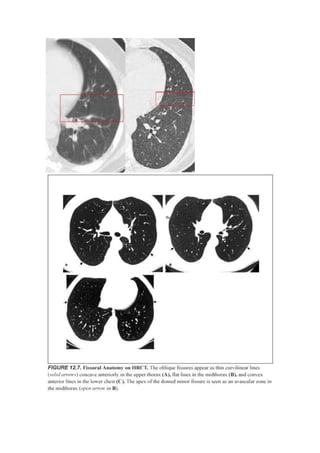

Cisuras normales

Las cisuras forman las superficies de contacto entre los lóbulos pulmonares. Aunque

podrían extenderse hasta el hilio –dando como resultado una separación lobar completa-

, normalmente son incompletas.

Cisuras mayores:

Las cisuras mayores que separan los lóbulos superiores (y en el lado derecho el lóbulo

medio) de los lóbulos inferiores, comienzan en o sobre el nivel de la quinta vértebra

dorsal y se extienden oblicuamente hacia abajo y hacia delante, discurriendo de una

forma más o menos paralela a la sexta costilla y terminando en el diafragma, unos pocos

centímetros de la pared pleural anterior.

La cisura mayor no se ve en la proyección PA y se identifica en la lateral. Cuando se

ven las dos cisuras mayores en la proyección lateral, la diferenciación entre ambas

depende de que se vea la unión de la cisura menor con la mayor en el lado derecho o

bien que sea visible la unión de alguna de ellas con el diafragma homolateral.

Cisura menor:

La cisura menor u horizontal separa el segmento anterior del lóbulo superior derecho

del lóbulo medio y es aproximadamente horizontal a la altura de la cuarta costilla en su

parte anterior. Se ve en las dos proyecciones en más de la mitad de los sujetos normales.

Su tamaño y posición son muy variables. La cisura menor incompleta es la forma más